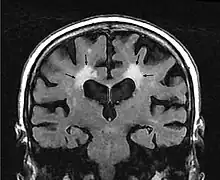

El término leucoaraiosis se utiliza en medicina para describir un hallazgo radiológico que consiste en la pérdida difusa de densidad en varias regiones de la sustancia blanca del cerebro, próximas a los ventrículos cerebrales y a la corteza cerebral profunda.[1] No es un diagnóstico, sino un hallazgo radiológico, y se detecta mediante imágenes obtenidas por diferentes técnicas, como la resonancia magnética nuclear y la tomografía axial computarizada.[2]

En la Tomografía Computarizada, la leucoaraiosis se observa como regiones con menor densidad, mas oscuras que las circundantes, es decir áreas hipodensas, en Imagen por Resonancia Magnética se define como lesiones con mayor intensidad de señal es decir áreas hiperintensas, por presentar un aspecto más brillante que las zonas aledañas. Estas imágenes pueden verse en las regiones próximas a los ventrículos cerebrales, corona radiata y centro semioval.[9] Se han utilizado escalas cualitativas como la de Fazekas para determinar el grado de las lesiones: